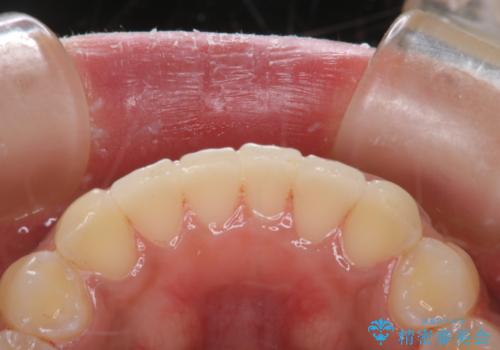

タバコのステインを徹底的に除去

- タバコによるステインを綺麗にしたいとのことでした。

PMTC60分コースを行いました。

PMTCでは、歯の表面の凸凹にミネラルを補給して、ツルツルの表面に仕上げます。定期的にPMTCを行うことにより、歯質の強化になり着色がつきにくい状態になります。